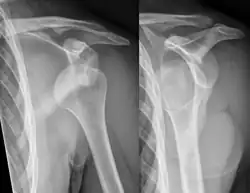

A diagnosis of shoulder dislocation is often suspected based on the person's history and physical examination. Radiographs are made to confirm the diagnosis. Most dislocations are apparent on radiographs showing incongruence of the glenohumeral joint. Posterior dislocations may be hard to detect on standard AP radiographs, but are more readily detected on other views. After reduction, radiographs are usually repeated to confirm successful reduction and to detect bone damage. After repeated shoulder dislocations, an MRI scan may be used to assess soft tissue damage. In regards to recurrent dislocations, the apprehension test (anterior instability) and sulcus sign (inferior instability) are useful methods for determining predisposition to future dislocation.

Anterior dislocation of the right shoulder. AP X ray -

Anterior dislocation of the right shoulder. Y view X ray.